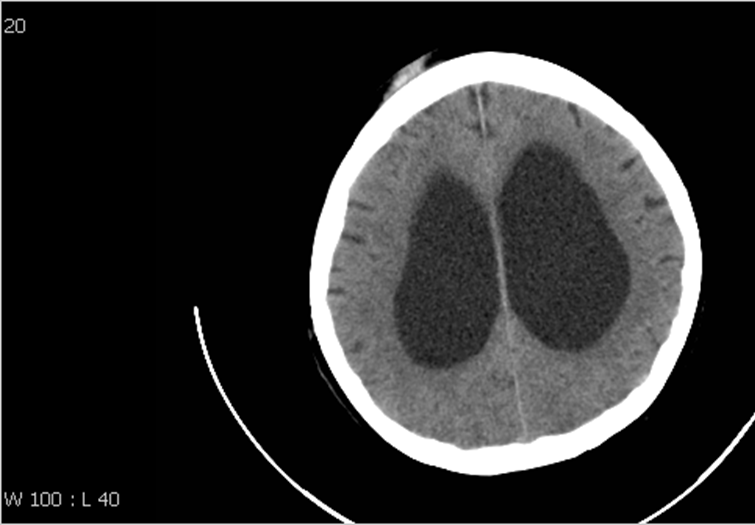

Exvacuo or normal pressure hydrocephalus?

Ex-vacuo hydrocephalus with diffuse cortical atrophy.

Absence of cortical atrophy below